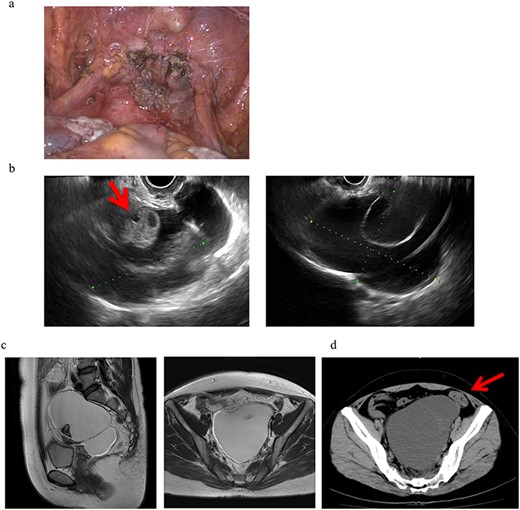

Four years and 6 months after surgery, she presented with lower left abdominal pain. A multilocular cyst, measuring ~10 cm, was detected on the vaginal stump by transvaginal US (Fig. 2b). Since the cyst was considered to be causing her symptoms, emergency surgery was performed. Adhesions were observed in the left adnexal region, and a clear yellow liquid was retained in the cavity formed by the adhesions (Fig. 3). The adhesions were removed by laparoscopic surgery and left adnexal excision was performed, which ameliorated her symptoms.

Clinical findings of case 2 (during surgery for PIC). (a) Strong adhesion between the sigmoid colon and pelvic wall in the left adnexal region. (b) When the sigmoid mesentery and left pelvic peritoneum were removed and the cyst was opened, a yellow transparent liquid was ejected. (c) The cavity formed by adhesions. (d) Left ovarian tissue inside PIC.